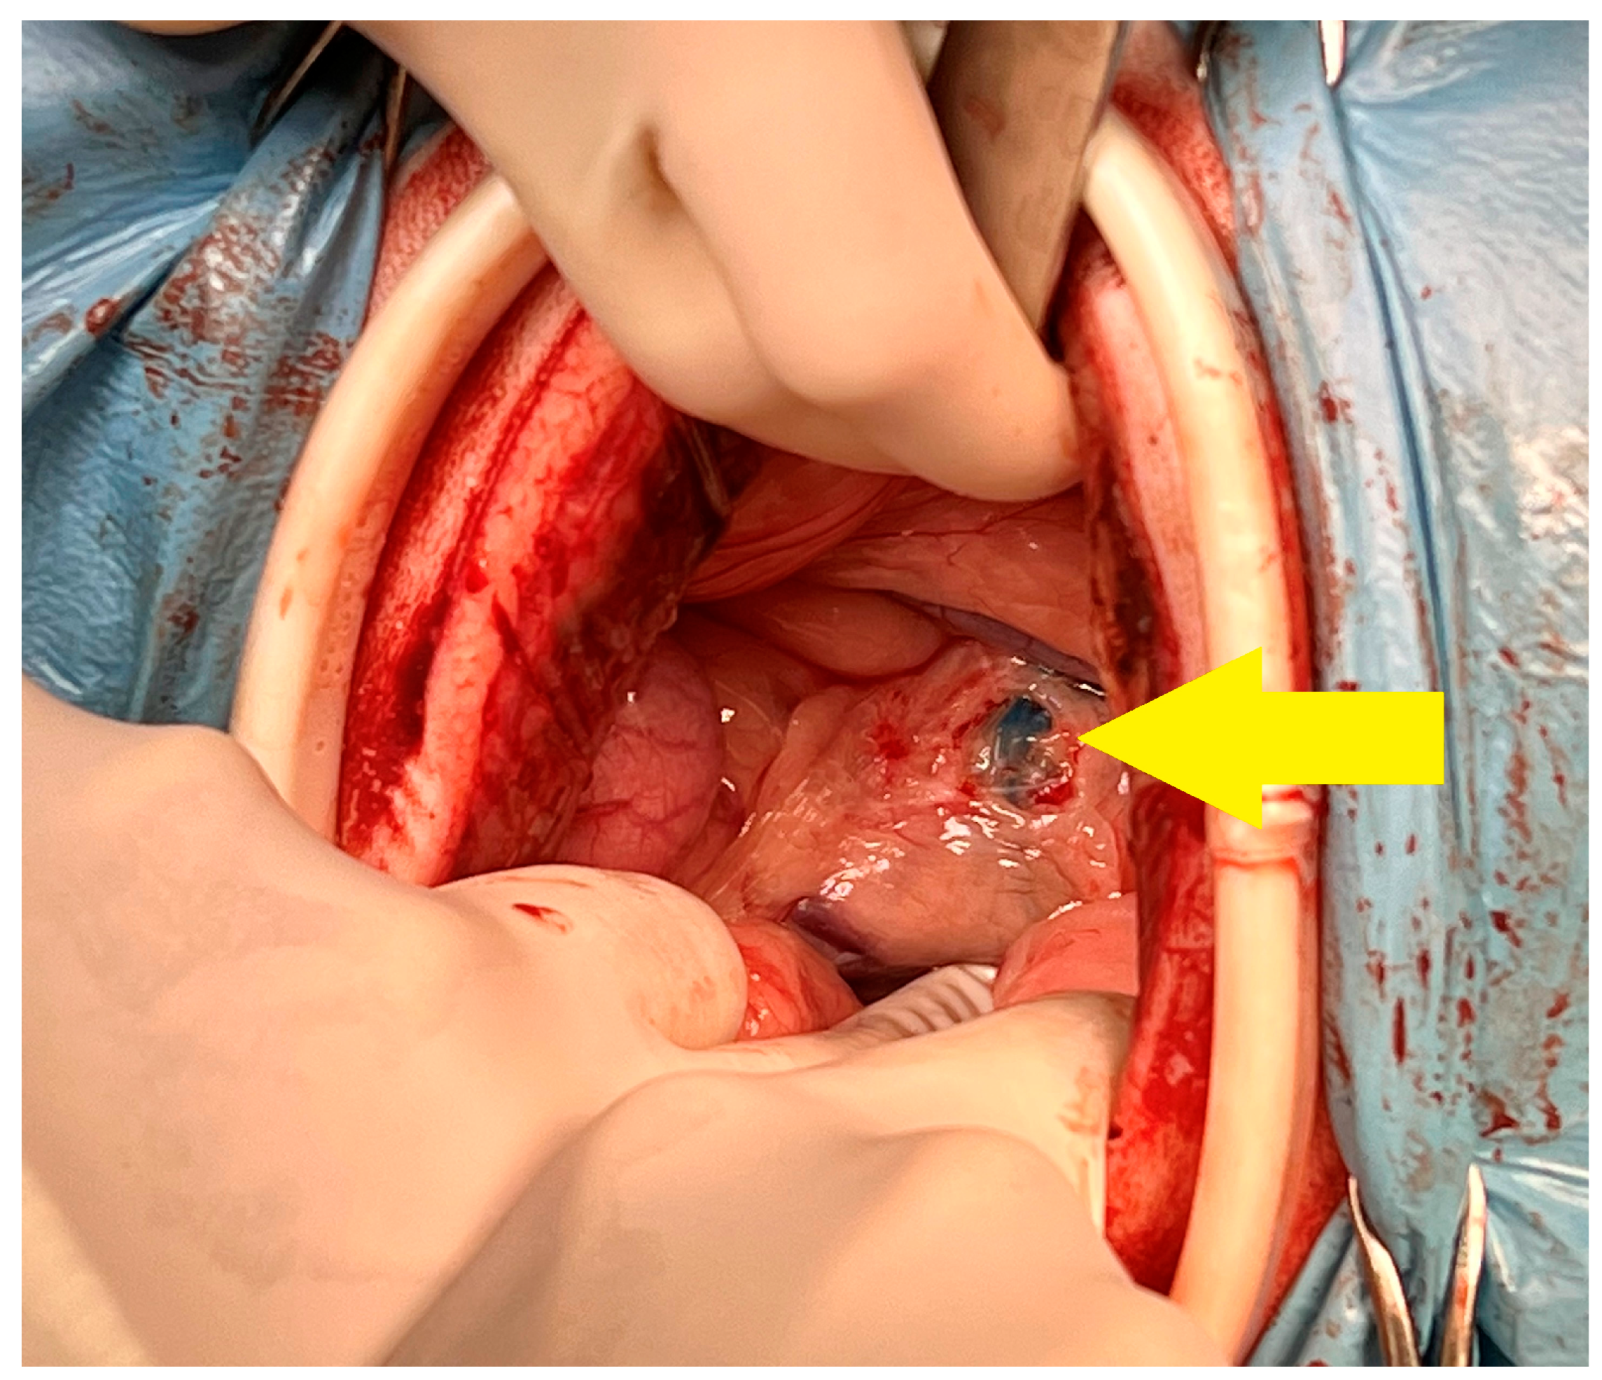

2. Materials and Methods

2.2. Surgery